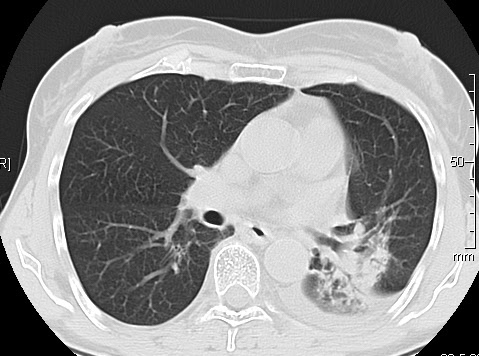

Kovid-19

O kovidu sam pisao puno puta. Evo nekih slika, radi poređenja

Nakon što pacijent bude izlečen od gripa ili kovida-19 pluća se mogu vratiti u normalu. To je razlika u odnosu na posledice upotrebe cigareta. Ovi snimci nisu postavljeni da bi se poredile bolesti, već da bi se ukazalo kako različite bolesti deluju na pluća. I ono što je veoma važno, ako neko dobije jednu od ovih bolesti, ne znači da u toku života neće dobiti drugu.